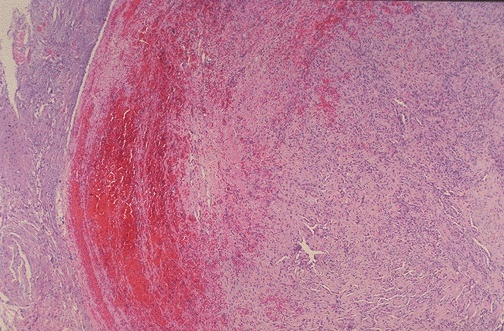

Here is a pelvic vein thrombus seen at low power microscopically. Note the thin muscular wall typical of a vein. The thrombus displays varying degrees of organization, reflecting its propagation over time.